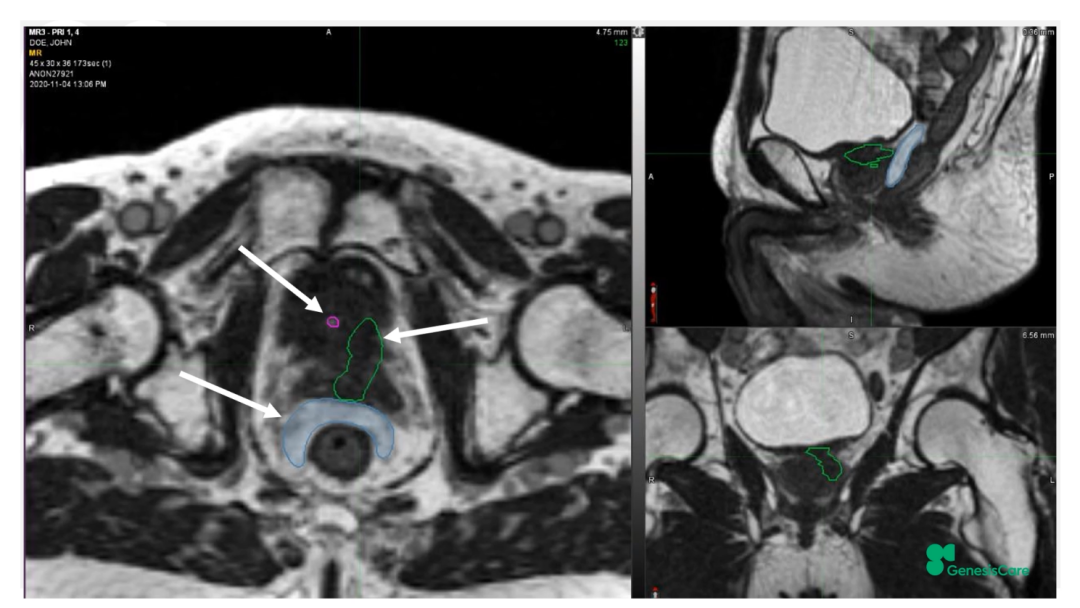

Dr. Camilleri介绍了一位72岁,在2006年接受了55Gy/20F放疗后复发的前列腺癌患者。当时它的PSA为28,局部晚期,期别为T3aN0M0。PET-CT显示前列腺左后部局部高代谢,活检也证实了这一点,并且活检结果表明肿瘤侵入左侧精囊腺底部。将其MRIdian MRI图像和PET-CT图像融合后,再根据活检结果确定靶区,见Figure 20-22,并制作放疗计划。放疗剂量为35Gy/5次,凝胶阻隔物很好地包含了直肠,见Figure 23,靶区和危及器官受量见Figure 24。患者于2020年12月接受治疗,他体质很好,在放疗期间和之后,坚持每周三次5公里跑步,始终未出现GU和GI毒性。他的PSA最低值为0.45,在2022年5月的随访数据中,睾丸激素水平回到了正常的33%。在2022年1月的放疗后PSMA PET的图像上,未见肿瘤高代谢见Figure 25。